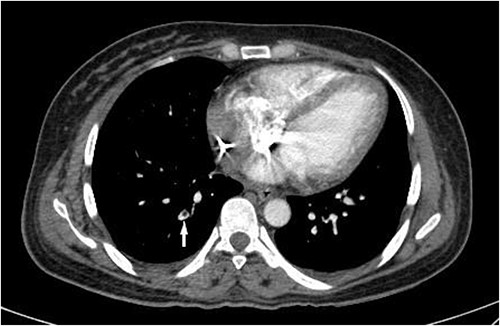

A subsequent emergent abdominopelvic computed tomography (CT) scan with intravenous (IV) and per os (PO) (via nasogastric tube) contrast administration was acquired, disclosing a large heterogeneous retroperitoneal pelvic hematoma extending up around the kidneys, anteriorly displacing the right kidney. Dilated tortuous ovarian arteries were also noticed, with the right-side artery surrounded by hematoma and pushed forward (Fig. 1). These findings indicated ovarian artery aneurysms (OAAs) and the right-side rupture due to delivery as the underlying cause of the massive hemorrhage.

IV and PO contrast-enhanced CT in portal phase shows a massive heterogeneous hematoma in the pelvic region, dominantly in the right lower quadrant. (a) An axial section at the level of abdominal aortic bifurcation, shows the dilated and anteriorly displaced right ovarian artery (arrowhead), indicating an aneurysm—its size is comparable to the common iliac artery (arrow). (b) A coronal reconstruction of the retroperitoneum demonstrates the extent of hematoma. The left ovarian artery manifests multiple aneurysms (arrows), and the obvious border between two regions of hematoma with different densities (paired arrowheads) shows separate bleeding episodes.